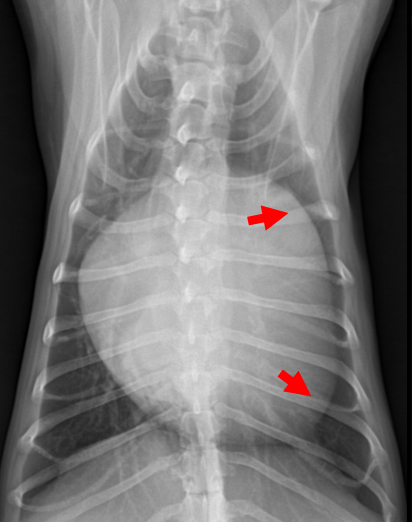

PDA

정의출생 후에도 동맥관이 닫히지 않아 대동맥 → 폐동맥으로 피가 흘러 발생한 좌심방 비대.

기전폐동맥 dilation → 폐와 폐정맥을 거쳐 좌심방까지 volume overload → 좌심방 비대

경과- 좌심방 비대 → carina를 자극해 기침 유발, MVI와 동일 기전.

- 기침, 객혈, 폐수종, left side congestive failures

영상

소견

- VD view의 1시 방향에 있는 mPA 커짐

- 심장 초음파로 duct 크기 판단 가능. Ao:mPA=1:1 이 정상인데, 폐동맥이 더 커짐.

- 좌심방이 더 커짐. (⇒ 심전도에서 P파가 넓어진 mitral P)